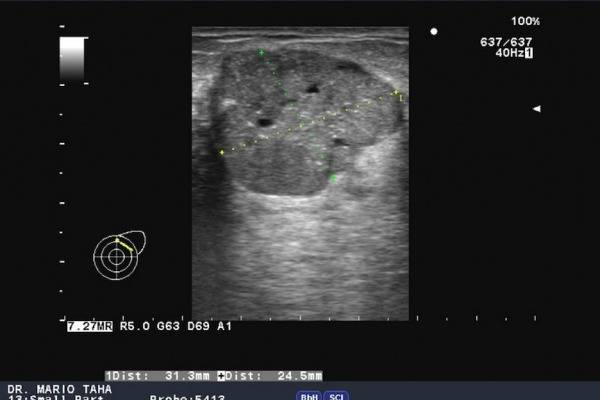

Мастит. Присутствуют очаговые образования вблизи от ареолярного сегмента. Контуры ровные, структура однородная с незначительными усилениями. Рисунок выглядит затушеванным. На нем четко различимы гомогенные зоны с участками воспаления. При наличии гнойных очагов расширяются альвеолы и протоки, которые окружены инфильтратом, имеющим вид сот.

Для проведения дифференциальной диагностики с маститом таким женщинам рекомендовано прохождение УЗИ грудных желез. Обычно врачи-сонологи описывают расширение протоков, наличие в них большого количества секрета, усиление кровотока.

Основная цель ультразвукового исследования в маммологии – диагностика жидкостных и акустических плотных образований в груди, а также видимый контроль за лечебными и инвазивными манипуляциями. УЗИ диагностика является эффективным способом определить лактостаз. Сканограммы отражают застой в виде чрезмерно расширенных протоков молочной железы. Особенно четко можно увидеть расширение отдаленных протоков и синусов. При лактостазе, в отличие от мастита, наблюдается сохранение структуры молочной железы при отсутствии примесей крови и лимфы в тканях.

Существует компенсированный и декомпенсированный лактостаз (рекомендуем прочитать: как делать массаж при лактостазе?). Определить наличие одного из них можно с помощью фармако-сонографической пробы с применением питуитрина. Для начала женщину просят максимально сцедить грудь, а затем проводят УЗИ. После определения диаметра млечных протоков в организм вводится 1 мл питуитрина (внутримышечно). По прошествии 15-20 минут ультразвуковое обследование повторяют.